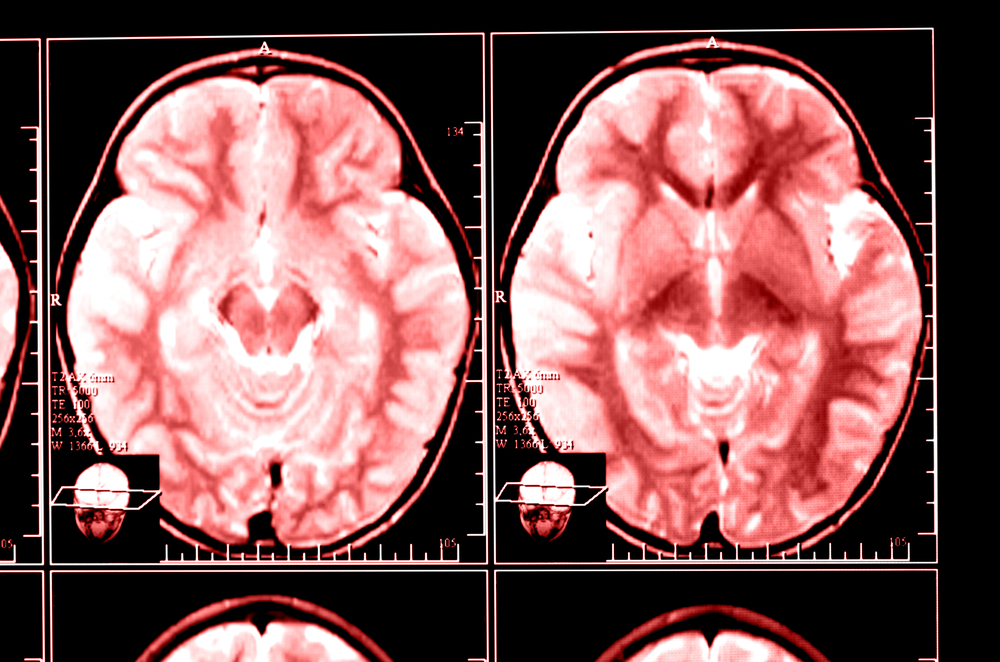

By analyzing activity in the brain’s visual cortex using fMRI scanners, researchers are able to know what an individual has been reading without any reference to the actual document itself. To do so, neuroscientists at a Dutch university taught a computer program how pixels from brain scans correspond to individual pixels in letters of the alphabet. While the study was limited to determining single letters seen by the experiment’s subjects, the results confirm that reconstructing brain images is an effective way to reconstruct what someone has seen.

The achievement improves on prior research which reconfigured the cerebral images of a person watching a video such that the rough outline and color of a shape, say of a tropical parrot, appeared on a computer screen. Researcher Marcel van Gerven, who led the Dutch experiment, said: Our approach is similar to how we believe the brain itself combines prior knowledge with sensory information. For example, you can recognize the lines and curves in this article as letters only after you have learned to read. And this is exactly what we are looking for: models that show what is happening in the brain in a realistic fashion.”